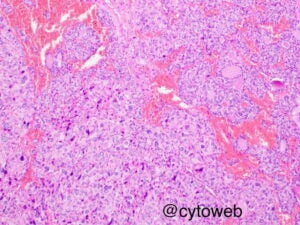

The important morphologic differential diagnosis to consider include:

1. Primary thyroid carcinoma – papillary thyroid carcinoma; possibly with dedifferentiation to anaplastic carcinoma

2. Metastatic poorly differentiated carcinoma

3. Treatment induced atypia

Anaplastic carcinoma of the thyroid is an important consideration based on the cytomorphology. However, the young age of the patient and the clinical history of neck irradiation and systemic chemotherapy makes anaplastic carcinoma less likely. There was also no rapid enlargement of the thyroid nodules in this case which is a hallmark of anaplastic carcinoma.

The diagnosis of metastatic carcinoma is less likely due to the young age of the patient and lack of significant clinical history of a primary cancer elsewhere.

Lymphomatous involvement (particularly Hodgkin) of the thyroid is also less likely because the atypical cells are present as single cells and as part of the follicles. No small lymphocytes are present in the background.

Treatment induced atypia may be considered because of the history of both radiation therapy and chemotherapy.